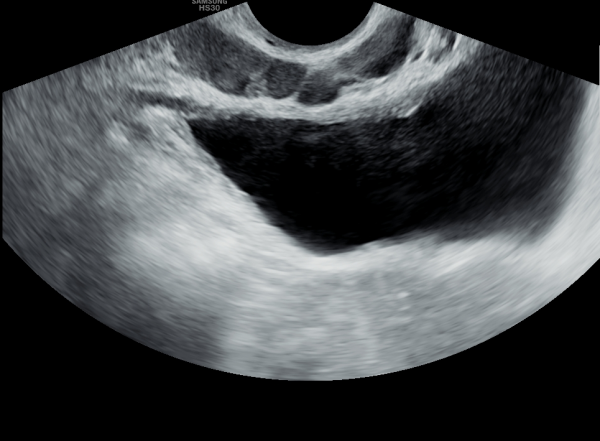

수년전부터 회음부 통증과 배뇨 장애로 내원 당일 검사한 경직장 전립선 초음파 검사상 사정관 입구의 미세 결석과

전립선의 낭종이 관찰되는 초음파 사진입니다.

A transrectal prostate ultrasound image taken on the day of the visit shows microcalcifications at the opening of the ejaculatory duct and cysts within the prostate, in a patient who had been experiencing perineal pain and voiding difficulties for several years.